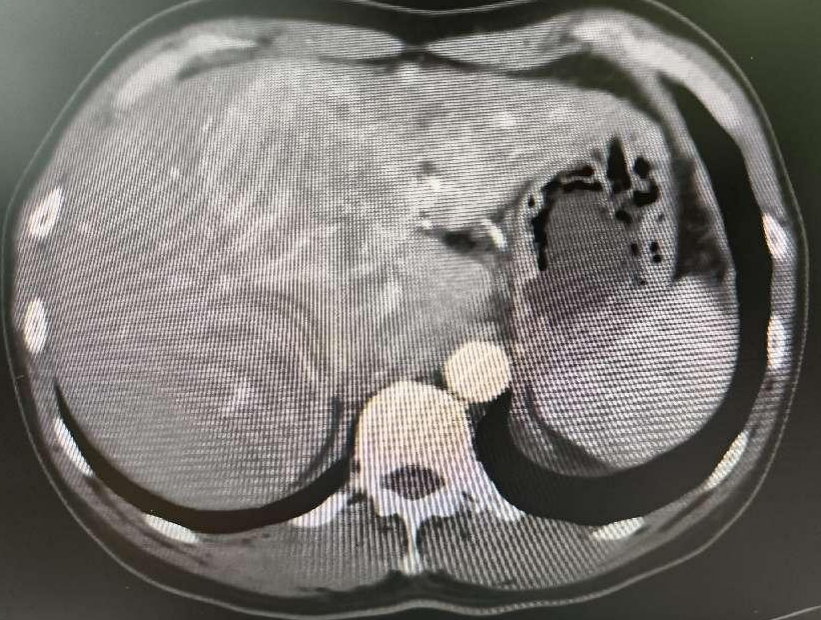

此后的数年,梁叔并没有规律的进行体检、复查,更没有考虑抗病毒治疗,直到1周前,他觉得自己的右侧肝区隐隐作痛,去医院检查被告知肝区可能有占位性病变。接下来的检查也明确了诊断:巨块型肝癌并门脉癌栓。